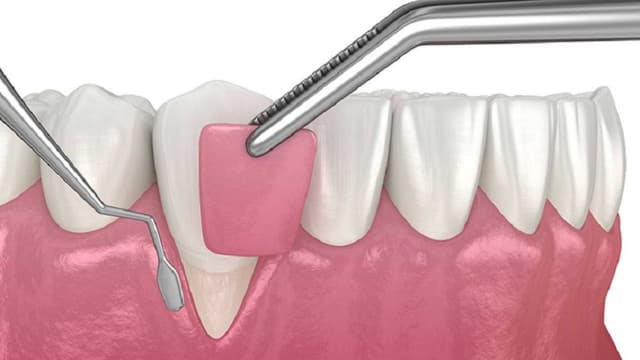

Mức giá phẫu thuật cắt lợi dành cho ai muốn biết

Phẫu thuật cắt lợi là một thủ thuật nha khoa phổ biến, nhằm mục đích điều chỉnh nướu răng để cải thiện sức khỏe răng miệng hoặc nâng cao tính thẩm mỹ của nụ cười. Quy trình này thường được áp dụng cho những người gặp vấn đề về lợi dư thừa, tụt lợi, hoặc […]